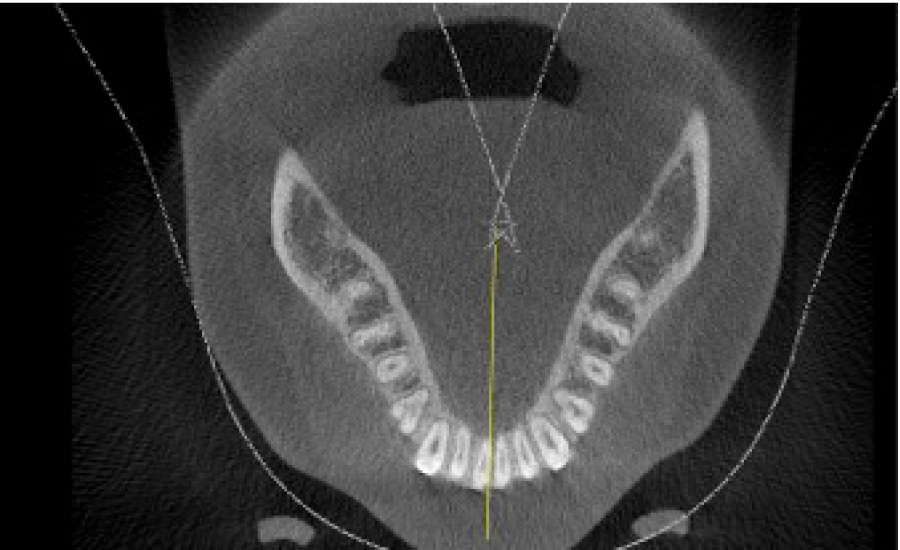

The overall treatment time was 6 months and there were no complications during and after the surgical procedure Facial balance was improved and the final occlusal relationships were good (Figure 5). Dental crowding was relieved thru mild expansion of the arches and proclination of upper and lower arches; it should be highlighted that the degree of proclination was very mild. Good parallelism of roots was also achieved (Table 1 and Figure 6).

The case described can be a good example how a new or different approach of treatment can cause controversy. In a traditional approach treating the case within the dimensions of the denture [20], this patient could be considered as a typical four first bicuspid extractions case but with surgical facilitated orthodontics the scope of orthodontic tooth movement can be increased [8,21] therefore in this case dental extractions were not done. It must be emphasized that alveolar augmentation was performed to strengthen the periodontal tissue; it is the third element of OAOTM: orthodontic forces, selective alveolar corticotomies and alveolar augmentation. The anterior crowding was relieved by expansion of the arches, mild proclination of the upper and lower incisors is observed in the cephalometric measurements (Table 1) and good alveolar width is observed in posttreatment CBCT scan in the lower arch (Figure 7).